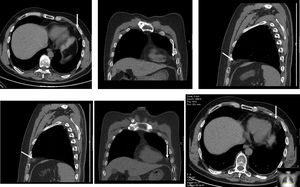

A healthy 50-year-old man was admitted to the emergency department for sudden intense pain located in the lower left anterior part of the chest, worsened by deep inspiration and with 10 hours of duration. The patient had had no similar episodes previously. He presented with tachypnea (29 cpm), tachycardia (heart rate 110 bpm) and diaphoresis. The electrocardiogram showed sinus tachycardia, without ischemic changes. Results of blood studies, arterial blood gas testing, cardiac markers, transthoracic echocardiogram and chest radiography were normal. Thoracic CT (Figure 1) showed an ovoid encapsulated mediastinal (epipericardial) fatty lesion in the left cardiophrenic angle with a soft tissue rim and intrinsic and surrounding soft tissue stranding, without pleural effusion. During hospitalization, the patient remained stable under analgesic therapy and was discharged with medication for symptomatic relief (non-steroidal anti-inflammatory drugs). After two and five months, thoracic CT showed a reduction of the lesion (Figures 2 and 3).